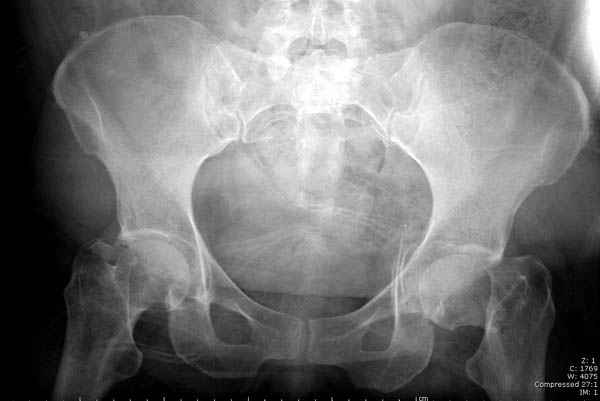

Долгое ожидание повышает риск АВН головки,

рекомендуется ургентная фиксация шейки в первые сутки, а в дальнейшем таз.

В данный момент скелетное вытяжение поучается через перелом шейки, а фиксированный перелом шейки будет участвовать в процессе вытяжения через каннюлированные шурупы.

Перелом шейки смогли зафиксировать через пару дней, ацетабулум до сих пор не оперирован, на вытяжении.

Из-за упущенного времени (три недели с момента

поступления) ацетабулум ведем консервативно.

На снимке ацетабулума редко встречающийся очень низкий перелом, наверное, трудно было репозицию через один доступ? Перелом как бы замкнулся в квадрилатеральной поврехности.